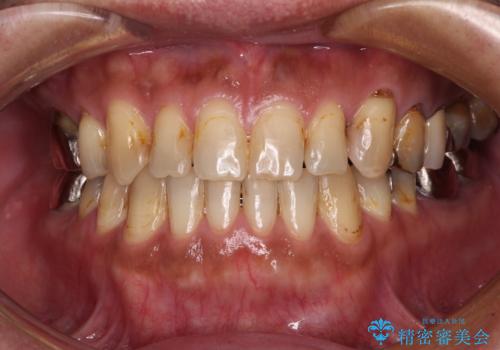

前歯の反対咬合をワイヤー矯正で改善して噛みやすく

矯正治療後は安定した咬み合わせとなり、顎の違和感がなくなったとのことでした。

今後はむし歯や銀歯を治療していく予定です。